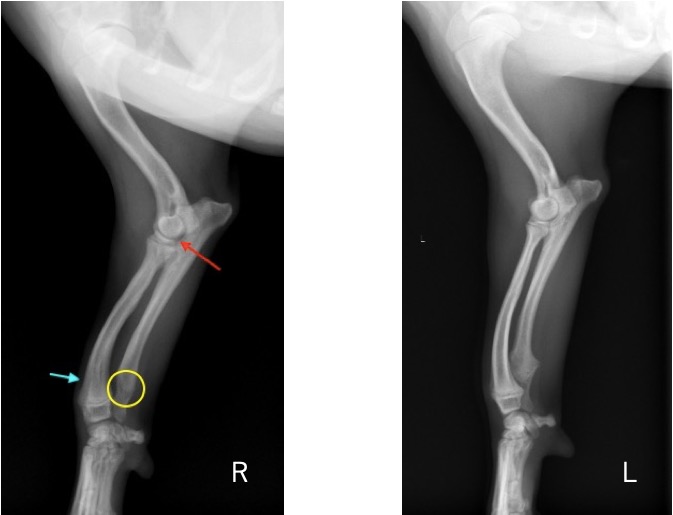

単純X線画像検査において、右側の尺骨遠位成長板領域の不透過性亢進、橈骨の頭側湾曲、鈎状突起と上腕骨顆の間隙が広がっている所見が認められたため、尺骨遠位成長板早期閉鎖が疑われました。

前腕の側面像 (黄丸;尺骨遠位成長板の不透過性亢進 青矢印:橈骨の湾曲 赤矢印:鈎状突起と上腕骨顆の間隙)

前腕の頭尾側像 (黄丸:尺骨遠位成長板の不透過性亢進 青矢印:橈骨の湾曲)

院内においても右前肢の挙上が認められ、単純X線画像検査を実施したところ、右側の橈骨遠位成長板領域の不透過性亢進、肘突起と上腕骨顆の間隙が広がっている所見が認められたため、橈骨遠位成長板早期閉鎖が疑われました。

前腕の側面像と頭尾側像 (黄丸と黄矢印:成長板の不透過性亢進 赤矢印:上腕骨顆と肘突起の間隙)